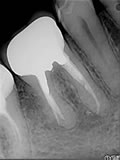

症例 25. リッジその2

下顎右側第一大臼歯の近心根にリッジが起こっている症例

治療前

治療中

治療後